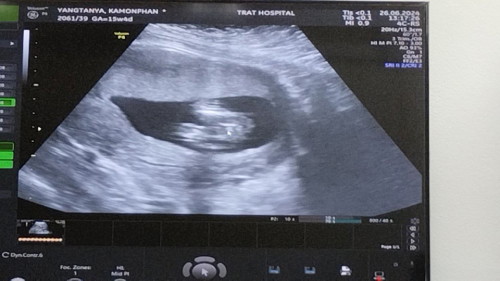

คุณหมอบอกน้องเป็นผู้หญิง แม่ๆช่วยคอนเฟิร์มหน่อยค่ะ ❤️#ขอบคุณสำหรับคำคอมเม้นล่วงหน้าค่ะ

ของเรา หมอบอกผู้หญิงค่ะ

ผู้หญิง100% ค่ะแบบนี้

หญิงค่ะแม่ ชัดเลย

ผู้หญิงค่ะ